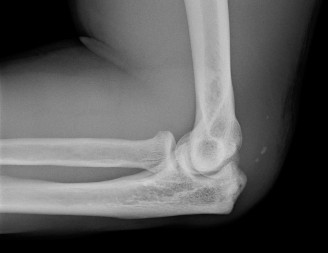

Treat a patient with axillary neuropathy? CASE 24 A 21-year-old, right-hand-dominant, male, college swimmer presents to clinic complaining of gradually worsening right shoulder pain for the past 6 months. He notes that his times at swim meets have been slowing with the onset of the pain but that he is still able to swim through the pain. Physical examination reveals: decreased muscle bulk over the infraspinatus fossa of the right shoulder compared with the contralateral side (shown in Fig. 2–64), full active range of motion, strength 4/5 for external rotation but otherwise normal strength, mild pain with cross-body adduction of the right shoulder, and mild tenderness to palpation over the AC joint. Imaging is shown in Figure 2–65.

Figure 2–64

Figure 2–65

The correct answer is (D). This patient’s atrophy of the infraspinatus muscle leading to weakness with external rotation and with preserved strength in the other rotator cuff muscles is likely due to neuropathic process of the suprascapular nerve at a

point along its course off the upper trunk of the brachial plexus on its way to innervate the supraspinatus and infraspinatus muscles. Choice A is incorrect as rotator cuff tendinitis would not present with muscle atrophy. AC joint arthritis (Choice C), while often presenting with tenderness to palpation over the AC joint and pain with cross body adduction, is also not usually associated with infraspinatus atrophy and would likely present with narrowed joint space or AC joint osteophytes on plain films, unlike this patient. Choice B is incorrect as the patient has full active range of motion, while adhesive capsulitis would more likely present as decreased active and passive range of motion.

You send the patient for an MRI, which is shown in Figure 2–66.

Figure 2–66

The correct answer is (C). The patient’s clinical examination findings of isolated

weakness in external rotation and atrophy of the infraspinatus muscle point to suprascapular nerve entrapment at a location past the exit point for the branch to the supraspinatus muscle. Also, MRI reveals a posterior labral tear with a paralabral cyst that is compressing the suprascapular nerve at the spinoglenoid notch. Choice A, while fitting with the patient’s clinical examination, does not fit with the MRI showing paralabral cyst. Choices B and D are incorrect because entrapment of the suprascapular nerve at the suprascapular notch by scapular body fracture or by the transverse scapular ligament (more common) would lead to weakness/atrophy in both supraspinatus and infraspinatus muscles as the suprascapular notch is proximal to the nerve branch point to the supraspinatus muscle.